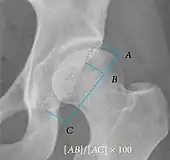

| Caput-sourcil angle[21] | ![]() |

Superior to the Tönnis angle in cases without joint space narrowing or subluxation.[21] The medial point of the sourcil is at the same height as the most superior point of caput femoris. | −6 to 12°[21]

|